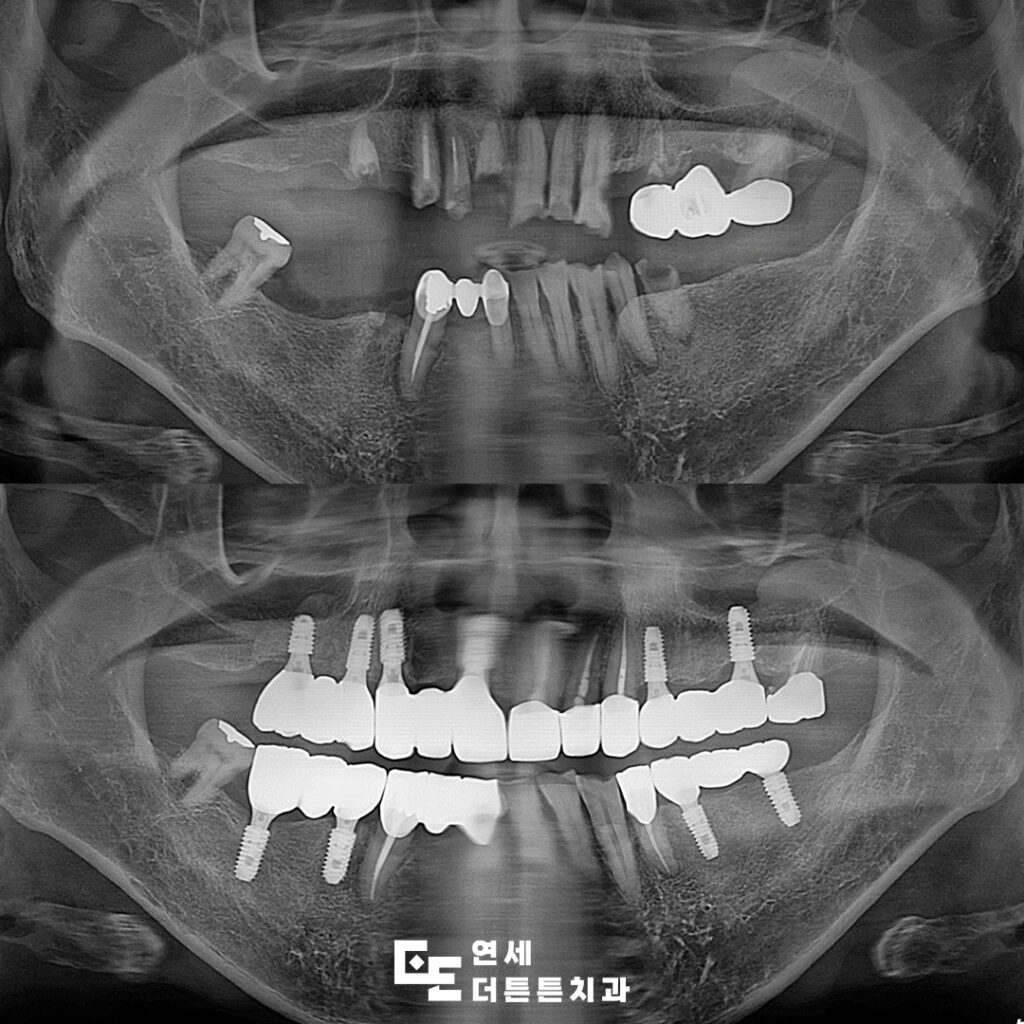

환자분께서는 구강 내 어금니 부위를 거의 상실하신 채로, 남아 있는 치아들도 부러져 제 기능을 하지 못해 치료 상담을 위해 방학역치과에 내원해 주셨습니다.

다수의 치아가 손상되거나 상실된 상태로 내원하였으며, 잔존 치아 또한 심한 우식과 변색, 구조적 약화가 동반된 상태였으므로 일부 치아는 보존이 어려운 상태였기 때문에 발치를 진행하였고, 남아 있는 치아 중 사용 가능한 치아는 신경치료 및 보강을 통해 최대한 활용하는 방향으로 치료를 계획하였습니다.

먼저 예후가 좋지 않은 치아들을 발치하고 결손 부위에는 임플란트를 식립하여 기능적인 지지 기반을 형성하였으며 최종 보철물이 들어가기 전 기간동안 사용하실 수 있는 임시틀니를 제작해 드렸습니다. 임플란트가 뼈에 제대로 붙기까지는 시간이 필요하며, 일반적으로 상악은 약 6개월, 하악은 약 4개월이 소요되어 그 기간동안 사용하시며, 최종 보철물에 대한 전반적인 상담도 충분히 진행할 수 있도록 하였습니다.